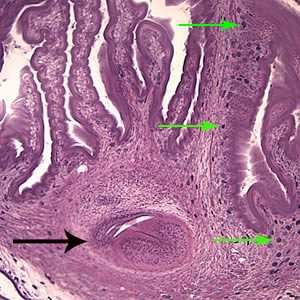

Larval Taenia solium.

Figure D: The extensive folding of the spiral canal and one sucker of the scolex (black arrow) are apparent. Calcareous corpuscles can be seen in the fibrous tissues (green arrows).